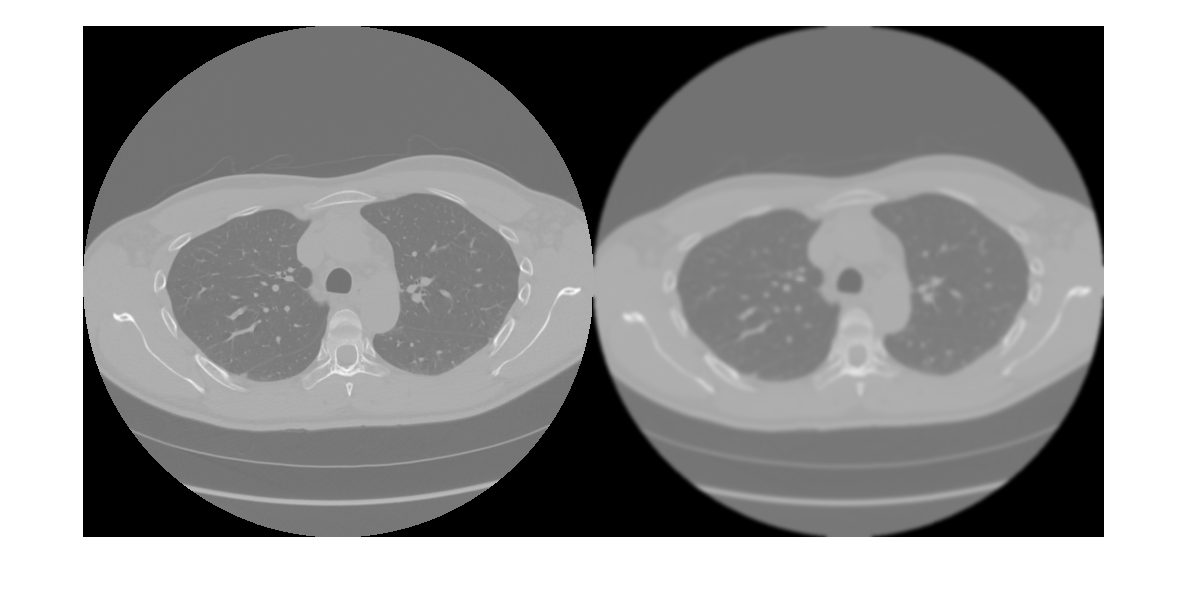

Visualize and compare the original and filtered pixel data.

figure

imshow([pixelData filteredPixelData],[])